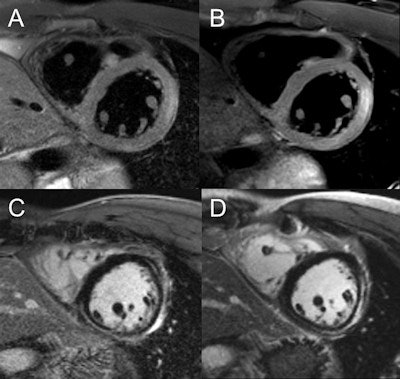

A: Single-dose (0.1 mmol/kg body weight) high-resolution (0.8 x 0.8 x 0.8 mm3) MR angiography in coarctation of the aorta (CoA). B: 3-tesla dynamic MR angiography performed at high temporal and spatial resolution. Images courtesy of Dr. Bernd Wintersperger.